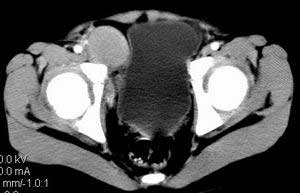

| 患者,男,9岁,因右下腹包块入院,血象不高,不规则发热,常超40度。 平扫: ![]() ![]() ![]() ![]() ![]() ![]() ![]() ![]() ![]() ![]() ![]() ![]() ![]() ![]() ![]() ![]() ![]() ![]() 增强: ![]() ![]() ![]() ![]() ![]() ![]() ![]() ![]() ![]() ![]() ![]() ![]() ![]() ![]() jiajie发言:骶椎右前区不规则软组织肿块,边缘光整,密度均匀,增强后均匀强化,右腹股沟区可见肿大淋巴结,临床有时发热,考虑淋巴瘤,儿童盆腔肿瘤应与神经母细胞瘤和横纹肌肉瘤鉴别。 longzhanghui发言:印象:盆腔右后壁不规则软组织肿块,并向前延伸.似为多个肿块融合,呈中等强化.初步考虑淋巴瘤. 听蝉观竹发言:右侧髂内、外组淋巴结肿大,从其形态和融合的情况看,同意大家意见-----考虑恶性病变,但是9岁男孩还要注意检查睾丸情况,有无隐睾? 常常类似情况是隐睾发生精原细胞瘤淋巴结转移,这个病例也要注意这一点!!! 广东凌发言:大家好,在这里我想说一下个人观点,我建议上传图片的同志能否辛苦一点就是把病史和图片都上传完整一点,比如这个病人的腹膜窗,并且这个病人的肠道的准备也是不怎么好,就从现有的质料看:病灶属于淋巴结肿大当无大的争议,有融合趋势,其内无坏死,边缘强化为主,故考虑:淋巴瘤!建议用腹膜窗看一下和肠道的关系! 阿圣发言:病灶属于淋巴结肿大当无大的争议,有融合趋势,其内无坏死,边缘强化为主,故考虑:淋巴瘤 结果是:淋巴瘤 病例来源:ct762。由宁静致远发布: http://www.radinet.com.cn/forum_view.asp?forum_id=4&view_id=2182 |